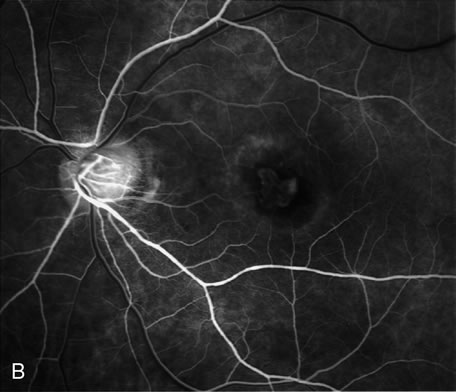

Furthermore, FA helps in recognizing two types of CNV: classic and occult. Classic CNV consists of a well-defined neovascular membrane, which is apparent in the early phase of the angiogram and shows late leakage of dye beyond its boundaries (Fig. 7 and 8). Occult CNV is seen on by FA as an area of late hyperfluorescence of undefined origin or as a neovascularized PED (Fig. 9 and 10 ). Mixed-type CNV is predominately classic or minimally classic depending on whether the classic component is more or less than 50% of the entire lesion (Fig. 11).

Fig. 7. Composite photograph of fluorescein angiography study in a patient with classic, subfoveal choroidal neovascularization (CNV) in the right eye. A The classic neovascular membrane appears as a well-defined area of hyperfluorescence in the early phases of the angiogram. There is leakage of dye from the classic net in the subretinal space throughout the study. B. In the late phase of the study, the edges of the CNV are fuzzy and indistinguishable.

Fig. 8. A. Color photograph of subfoveal classic choroidal neovascularization (CNV). The neovascular membrane appears as a dirty gray, subfoveal lesion surrounded by exudative neurosensory detachment. B–D. Fluorescein angiography demonstrates early hyperfluorescence and late leakage of the CNV.